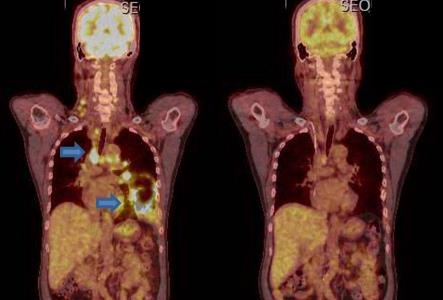

폐암의 생존율

폐암의 5년 생존율은 1기 70~90%, 2기 50~60%, 3기 15~35%, 4기 5~10% 로 나타나고 있습니다. 치료가 빠를수록 생존율이 높아집니다. 폐암의 조기 발견을 위해서는 정기적인 검진이 필수적입니다. 금연을 하면 폐암의 위험을 줄일 수 있지만 5년 차부터 감소하며 금연 15년 후에는 1.5~2배 감소합니다.